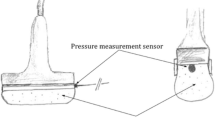

A beanbag was positioned underneath each pig to maintain the supine position throughout the experiment (Fig. 7). The tibialis anterior muscles of both hind limbs of the pig were selected as the target muscles. Both muscles were identified under ultrasound guidance and marked with a pen. Two ultrasound imaging machines, Aplio i700 (Canon Medical Systems, Tochigi, Japan) were used to quantify the shear modulus of elasticity of the tibialis anterior muscle in the SEG and to quantify the echogenicity and arterial blood flow velocity in the EG. In the SEG, the i18LX5 linear probe was used to collect SWE images of each hind limb at 15MHz. Each probe was placed longitudinally to the marked tibialis anterior muscle belly and angled 90° with the skin surface to maintain the same contact pressure and position throughout the experiment using the three-dimensional (3D) printed probe holder with an adjustable cell phone holder fixed on the experimental table (Fig. 7). In the EG, the PLT-1005BT linear probe was used to collect echogenicity data and arterial blood flow velocity of each hind limb at 11MHz with 82 gain, and each probe was placed transversely to the marked tibialis anterior muscle belly with the other experimental conditions similar to the SEG (Fig. 7). A 24-gauge heparinized IV catheter (Jelco® IV catheter radiopaque, Smith Medical, Ashford, UK) was inserted into the carotid artery to measure the systolic and diastolic central blood pressure. It was connected to a pressure-transducing device (AMK 150®, Ace Medical Co., Seoul, South Korea) and continuously monitored each pig’s condition throughout the experiment using a patient monitor (BM5, Bionet Co. Berlin, Germany). A 16-gauge heparinized IV catheter (Jelco® IV catheter radiopaque, Smith Medical, Ashford, UK) was gently inserted in the intermuscular plane between the tibialis anterior and peroneus muscles under ultrasound guidance to measure the ICP of the anterior compartment of the porcine leg, which was also connected to a pressure-transducing device and continuously monitored.

According to Gifford et al.48 and Sanderson et al.49, there would not be any changes in muscle during those ischemic periods except possible edema. Thus, a total of seven measurements on both sides were obtained, as indicated in Fig. 7. CS was induced by ligating the CIA for 6 h and reperfusing the CIA. The measurement time points were as follows: (1) right after the ligation of the CIA as baseline; (2) before reperfusion of the CIA indicated as BR; (3) right after reperfusion of the CIA indicated as AR_0 min; (4) approximately 30 min after reperfusion of the CIA indicated as AR_30 min; (5) approximately 60 min after reperfusion of the CIA indicated as AR_60 min; (6) approximately 90 min after reperfusion of the CIA indicated as AR_90 min; (7) approximately 120 min after reperfusion of the CIA indicated as AR_120 min. In the SEG, a minimum of five SWE images were recorded at each time point, along with the systolic and diastolic central blood pressure recordings, and the ICP of both legs. In the EG, one B-mode image and blood flow image of the anterior tibial artery (Fig. 8) were recorded at each point along with the systolic and diastolic central blood pressure recordings, and the ICP of both legs.

Echogenicity was calculated using the ultrasound imaging machine based on the average value of the brightness in the region of interest (ROI) from the transverse image collected of the yellow trace of the tibialis anterior muscle compartment and the freehand drawing function (Fig. 10).